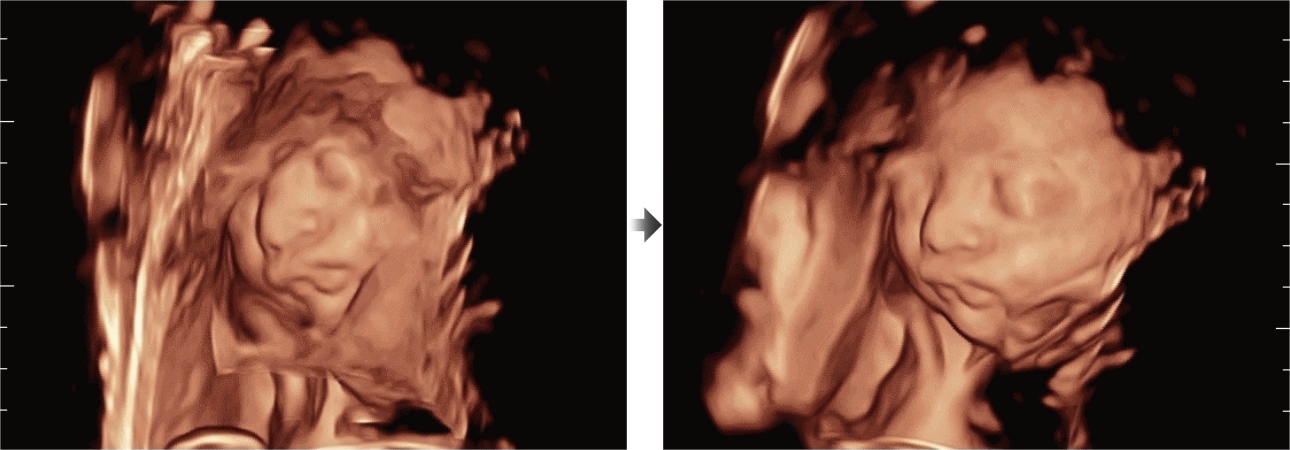

Fin dalla sua fondazione Mindray esplora continuamente nuovi modi per migliorare l'affidabilit├Ā diagnostica. Equipaggiata con la pi├╣ rivoluzionaria tecnologia ZONE Sonography?, la nuova piattaforma ZST+ di Resona 7 porta la qualit├Ā dell'immagine ecografica ad un livello superiore con l'acquisizione per zone e l'elaborazione dei dati canale.

Oltre alla qualit├Ā delle immagini di livello eccellente, Resona 7 migliora anche le capacit├Ā di ricerca clinica il rivoluzionario V Flow per la valutazione emodinamica vascolare, e l'acquisizione piani pi├╣ intelligente dal set di dati 3D per la diagnosi del sistema nervoso centrale fetale. Combinando il pi├╣ intuitivo funzionamento multi-touch basato su gesti e tutte le caratteristiche cliniche essenziali, Resona 7 sta veramente portando nuove tendenze nellŌĆÖinnovazione dellŌĆÖecografia.